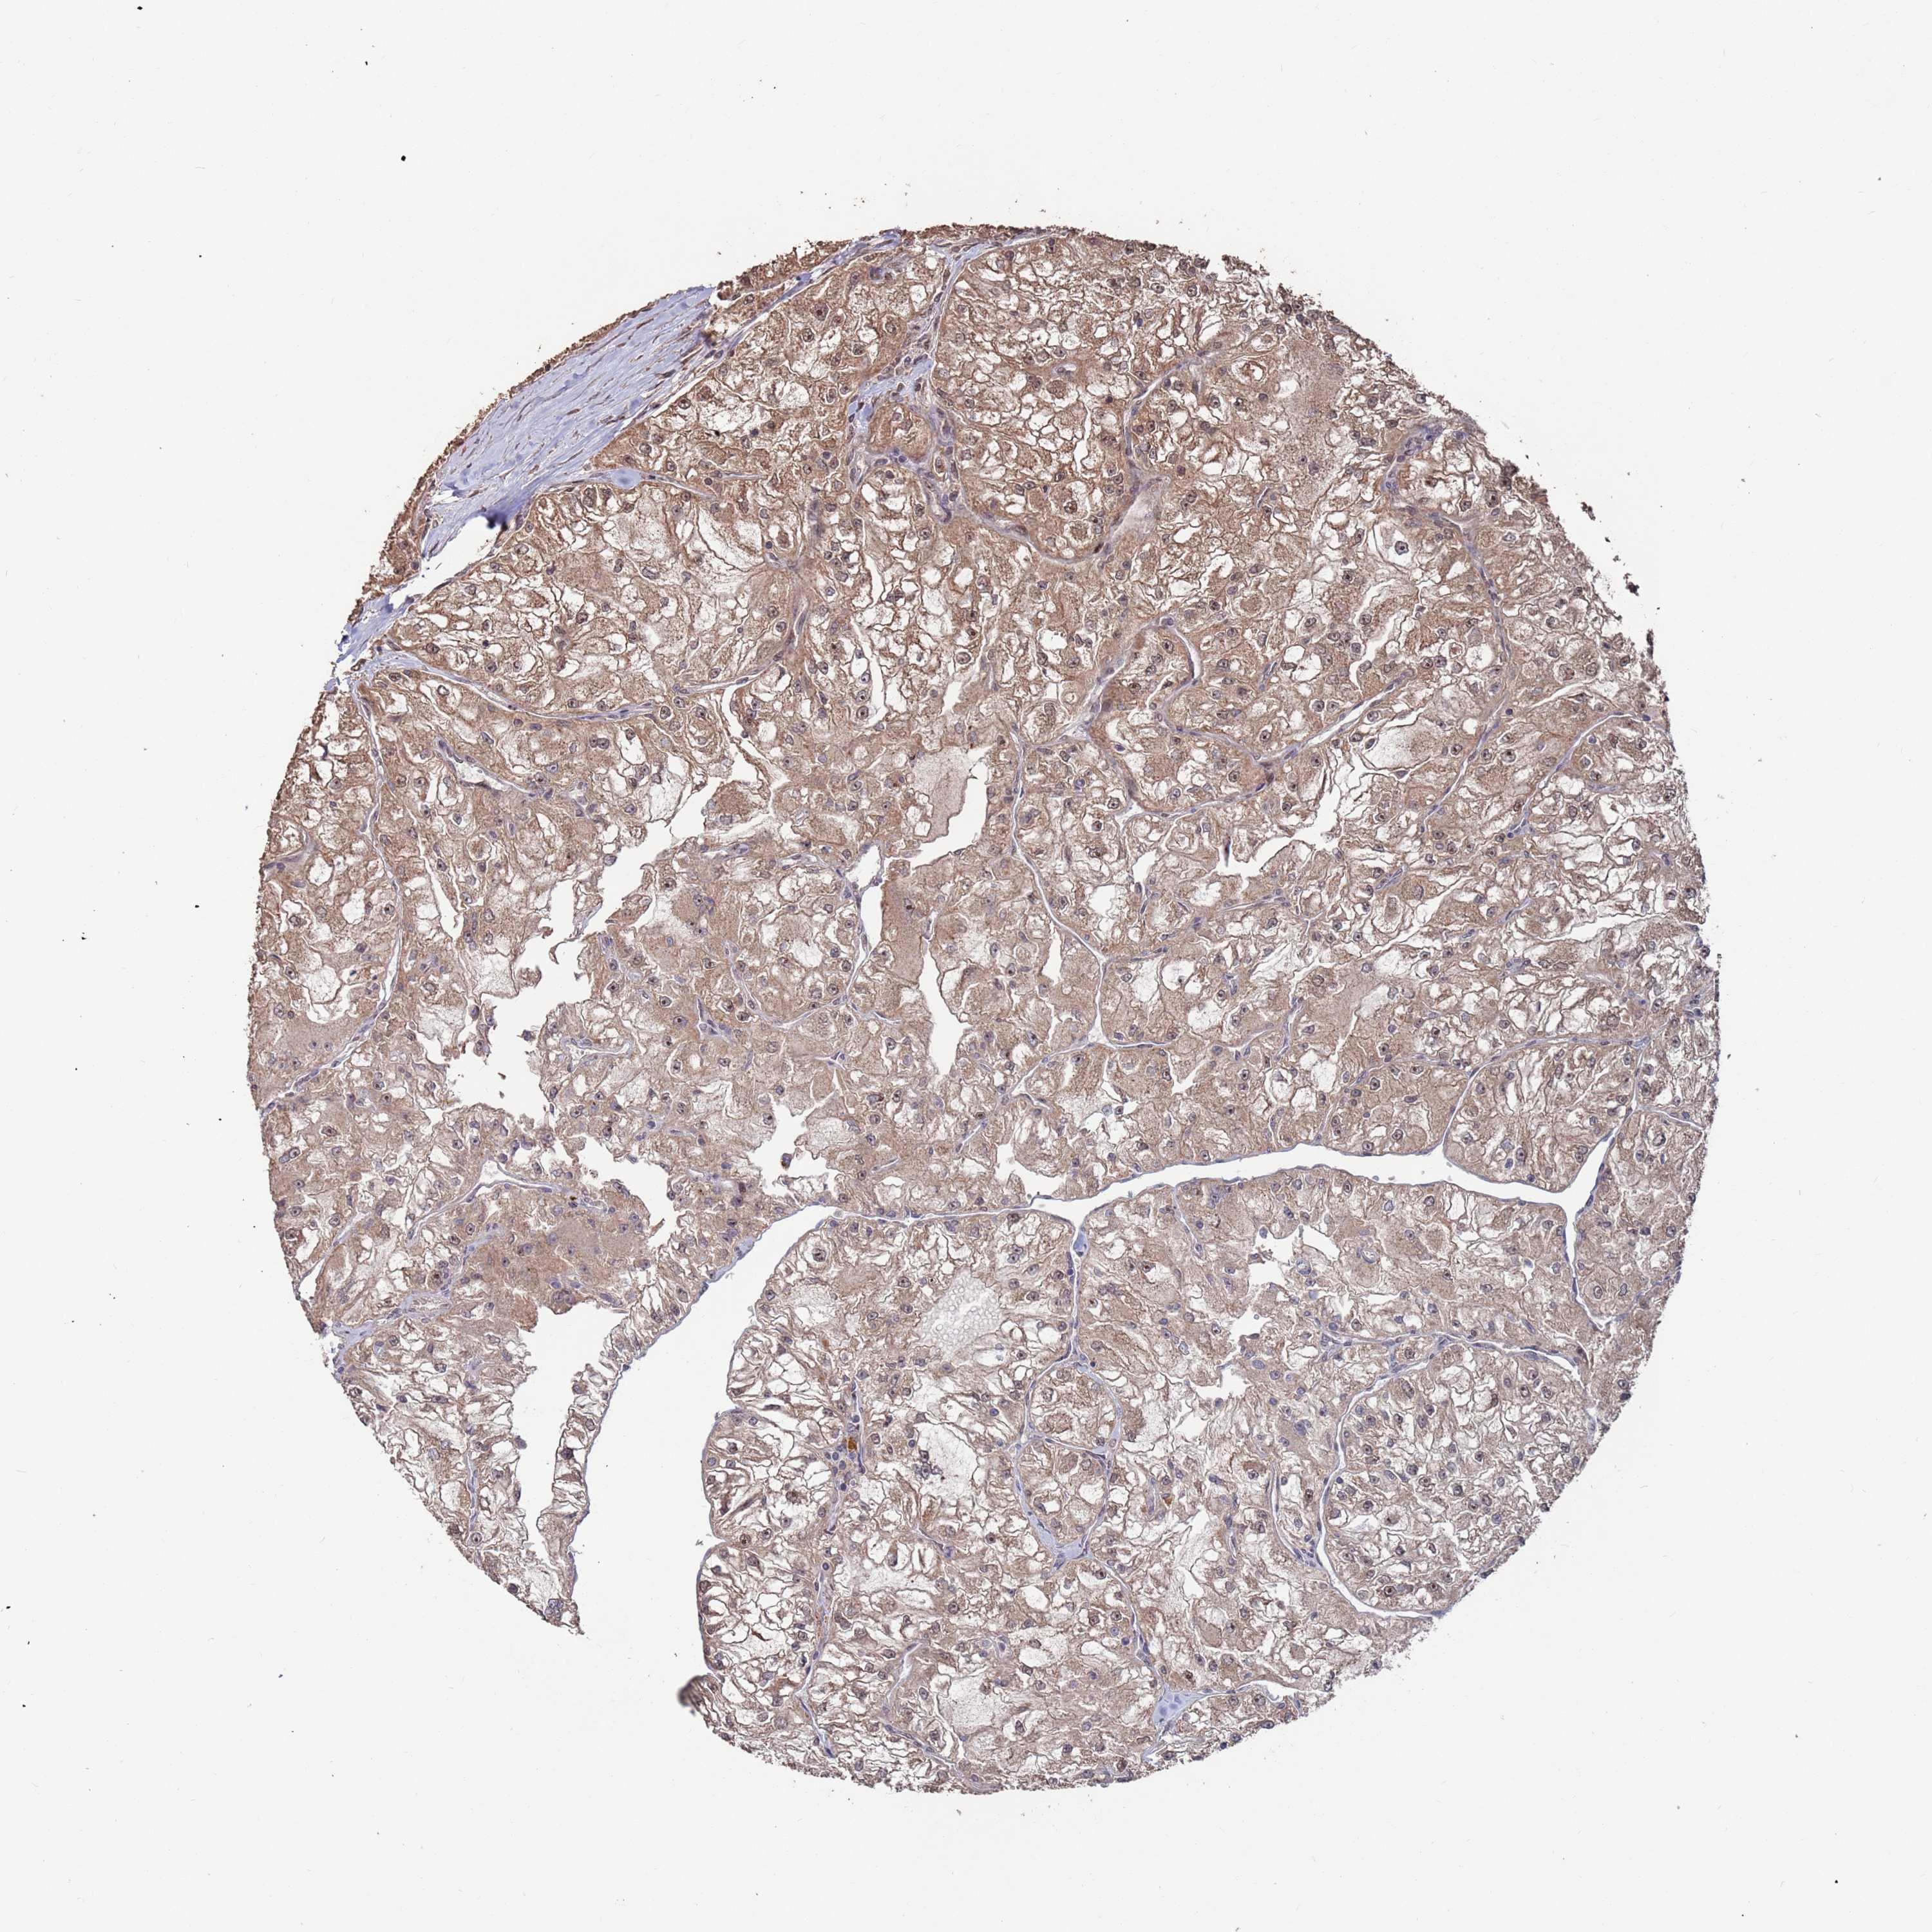

KIDNEY RENAL CLEAR CELL CARCINOMA (VALIDATION) - Interactive survival scatter ploti

The Survival Scatter plot shows the clinical status (i.e. dead or alive) for all individuals in the patient cohort, based on the same data that underlies the corresponding Kaplan-Meier plots. Patients that are alive at last time for follow-up are shown in blue and patients who have died during the study are shown in red.

The x-axis shows the expression levels (FPKM) of the investigated gene in the tumor tissue at the time of diagnosis. The y-axis shows the follow-up time after diagnosis (years). Both axes are complimented with kernel density curves demonstrating the data density over the axes. The top density plot shows the expression levels (FPKM) distribution among dead (red) and alive patients (blue). The right density plot shows the data density of the survived years of dead patients with high and low expression levels respectively, stratified using the cutoff indicated by the vertical dashed line through the Survival Scatter plot. This cutoff is automatically defined based on the FPKM cutoff that minimizes the p-score. The cutoff can be changed by dragging the vertical line or by entering a cutoff value in the square labeled "Current cut-off".

Under the Survival Scatter plot the p-score landscape (black curve; left axis) is shown together with dead median separation (red curve; right axis). Dead median separation is the difference in median mRNA expression between patients who have died with high and low expression, respectively. It is calculated as follows: median FPKM expression of dead patients with high expression - median FPKM expression of dead patients with low expression. This is intended to aid the user in visually exploring custom cutoffs and the associated p-scores and dead median separation.

Individual patient data is displayed and can be filtered by clicking on one or more of the category buttons on the top of the page. Categories describing expression level and patient information include: high, low, alive, dead, female, male and tumor stages. The scale of the x-axis can be toggled between linear and log-scale by clicking on the "x log" button. Mouse-over function shows TCGA ID, patient information and mRNA expression (FPKM) for each patient.

& Survival analysisi

Kaplan-Meier plots summarize results from analysis of correlation between mRNA expression level and patient survival. Patients were divided based on level of expression into one of the two groups "low" (under cut off) or "high" (over cut off). X-axis shows time for survival (years) and y-axis shows the probability of survival, where 1.0 corresponds to 100 percent.

PRR7 is not prognostic in Kidney Renal Clear Cell Carcinoma (validation)

: 12.93

Average pTPM 11.3

Number of samples 100